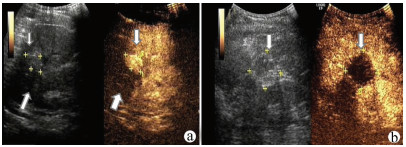

Guideline for ultrasonic diagnosis of liver diseases

2021, 37(8): 1770-1785. DOI: 10.3969/j.issn.1001-5256.2021.08.007

Abstract(3025) HTML (6526) PDF (9311KB)(794)

Abstract:

Ultrasound is a non-invasive, real-time, inexpensive, radiation-free and easily repeatable method, usually used for liver imaging. In recent years, new ultrasound examination techniques for liver diseases such as contrast-enhanced ultrasound and elastography have been rapidly developed, which can effectively identify intrahepatic space-occupying lesions, assess the degree of liver fibrosis and portal hypertension, and monitor the effects of treatment. Therefore, these technologies play an important diagnostic role in clinical liver diseases and have therapeutic interventional value. This guideline classifies the instrument set-up, patient preparation, and physician examination methods through multimodal ultrasound examinations (gray-scale ultrasound, color Doppler ultrasound, contrast-enhanced ultrasound, elastic ultrasound) for liver diseases. In addition, liver diseases multimodal ultrasound technology diagnostic criteria for diffuse hepatic lesions (inflammatory lesions, fibrosis, and sclerosis), multiple space-occupying lesions, and interventional procedures have been defined and standardized. Concurrently, we also recommend the ultrasound monitoring time interval and diagnostic report writing standard for liver diseases.